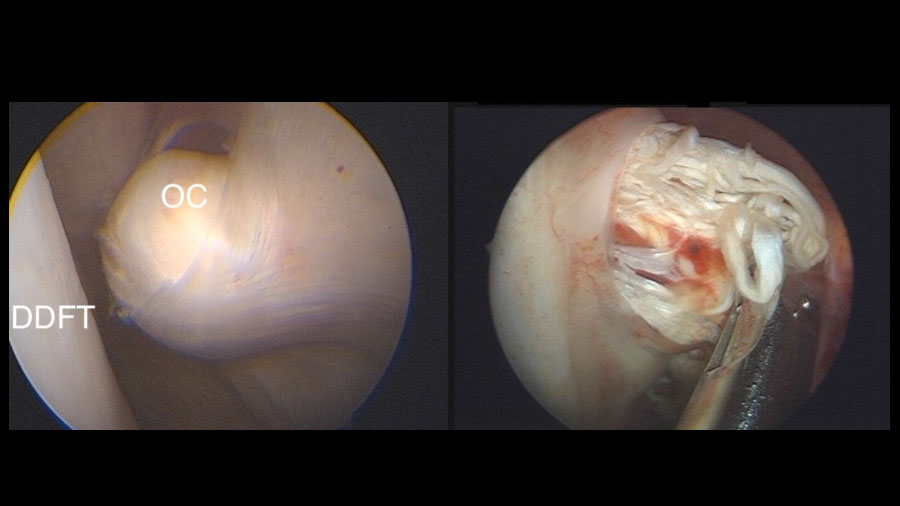

The DDFT tear (and any damage to SDFT or RH-DDFT) is debrided with the resector and the sheath lavaged before routine skin closure and bandaging.

Representative clinical case

A recent case involved a 3‑year‑old Thoroughbred gelding with acute lameness and carpal sheath swelling, having successfully completed multiple races. Radiographs identified a large osteochondroma, and ultrasound confirmed marked disruption to the DDFT. Standard tenoscopic surgery was completed as above, identifying the osteochondroma extending deep into the DDFT. Removal was confirmed using radiography intra-operatively after debridement of the tendon lesion.